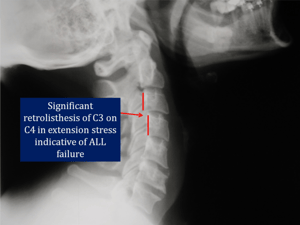

Although a standard x-ray series will not typically show ligament damage, stress view x rays of the cervical or lumbar spine often uncover these so-called “hidden injuries”.

In the cervical spine radiographs are taken with the neck in flexion, extension, and lateral bending to the left and right. These views must be taken on patients who have sustained trauma of any nature in order to evaluate potential ligament failure.

The cervical film at the top of the page is an extension view taken a few days after the patient was involved in a motor vehicle collision. No disc pathology was found on a standard MRI, but these x-rays reveal clear evidence of significant damage to the Anterior Longitudinal Ligament (ALL).